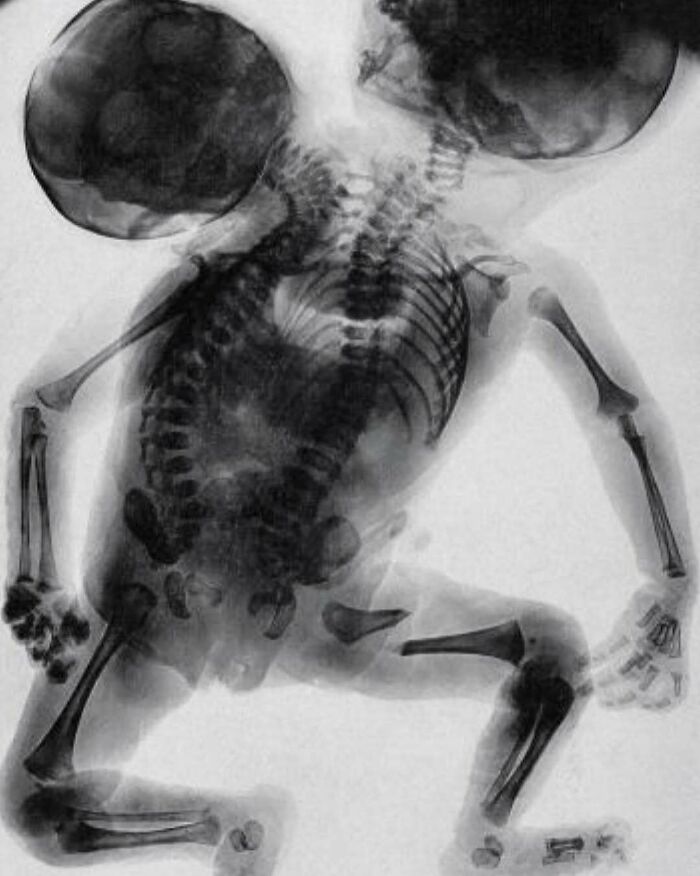

#53

An X-ray of conjoined twins born with two backbones and two heads

Conjoined twins are two babies who are born physically connected to each other. Conjoined twins develop when an early embryo only partially separates to form two individuals. Although two babies develop from this embryo, they remain physically connected — most often at the chest, abdomen or pelvis. Conjoined twins may also share one or more internal body organs. Though many conjoined twins are not alive when born (stillborn) or die shortly after birth, advances in surgery and technology have improved survival rates. Some surviving conjoined twins can be surgically separated. The success of surgery depends on where the twins are joined and how many and which organs are shared. It also depends on the experience and skill of the surgical team.